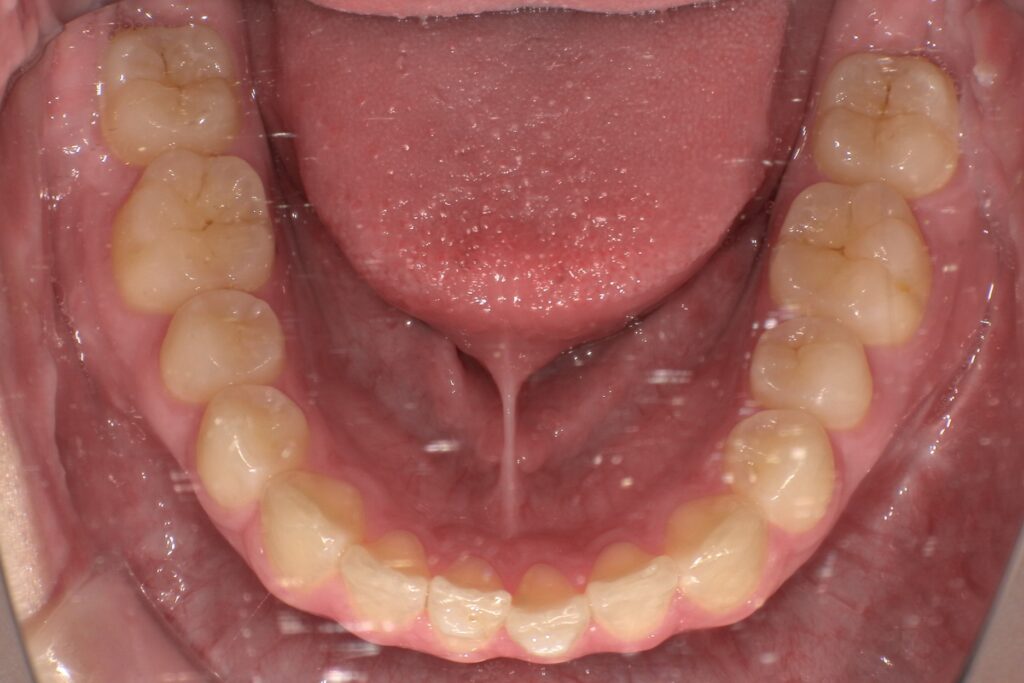

歯が少しだけズレてきた、隙間が開いてきた↓

見た目が気になる、前歯中心の後戻り↓

中等度の後戻り(複数の歯のズレ)

上下の歯並びが少しガタついてきた